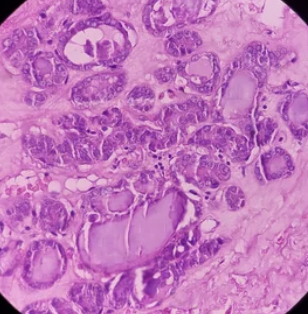

모낭염은 털이 자라는 모낭에 세균 감염이 발생하여 생기는 염증성 질환입니다. 여드름과 비슷해 보이지만, 모낭염은 털 주변에 붉은 뾰루지와 고름이 생기고 가려움증을 동반하는 것이 특징입니다.

모낭염의 주요 원인은 세균 감염입니다. 황색포도상구균이 가장 흔한 원인균이며, 그 외에도 녹농균, 그람음성균 등 다양한 세균이 모낭염을 일으킬 수 있습니다.

2. 모낭염, 어떤 증상이 나타날까요?

- 붉은 뾰루지: 털 주변에 붉은 뾰루지가 생깁니다.

- 고름: 뾰루지 안에 고름이 차는 경우도 있습니다.

- 가려움증: 심한 가려움증을 동반하기도 합니다.

- 통증: 염증이 심해지면 통증을 느낄 수 있습니다.

- 열감: 염증 부위에 열감이 느껴질 수 있습니다.